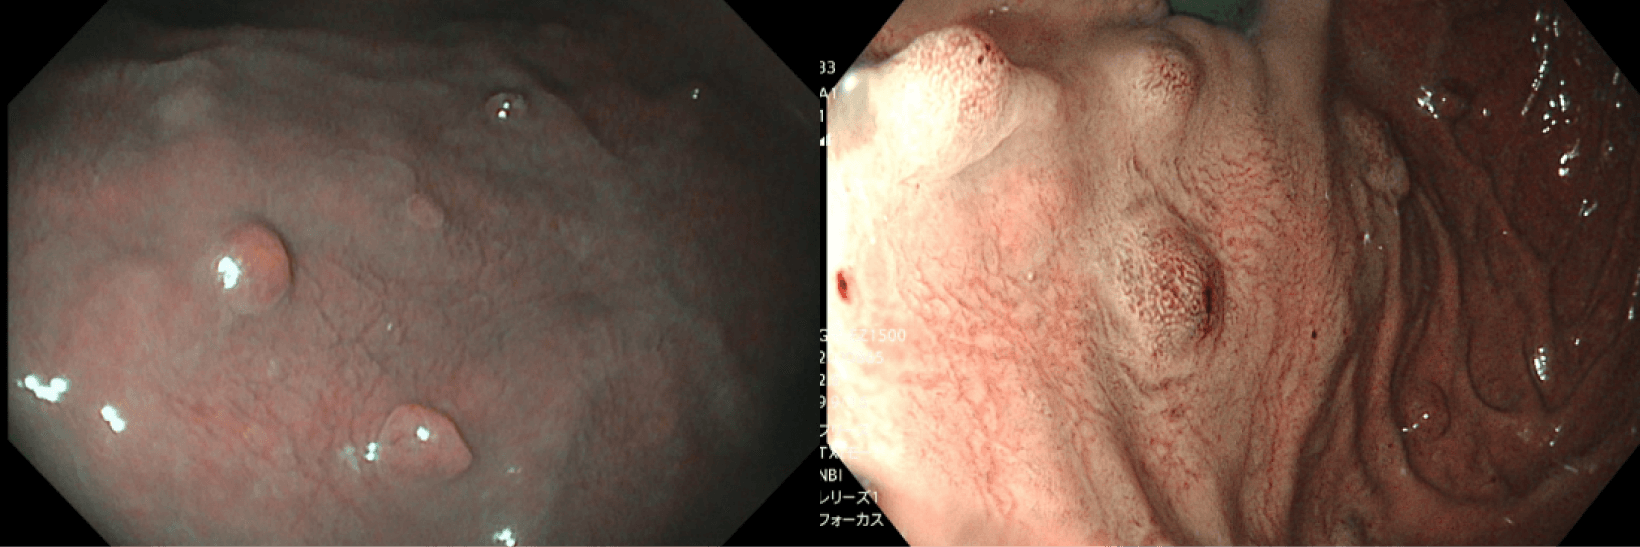

上記写真は同一患者に対しNBIという特殊光で撮影したものです。左は190N(当院所有のものでなく借り物)、右は1200Nで撮影したものです。左ではポリープの表面模様が不鮮明ですが、右はくっきりと模様が確認できます。